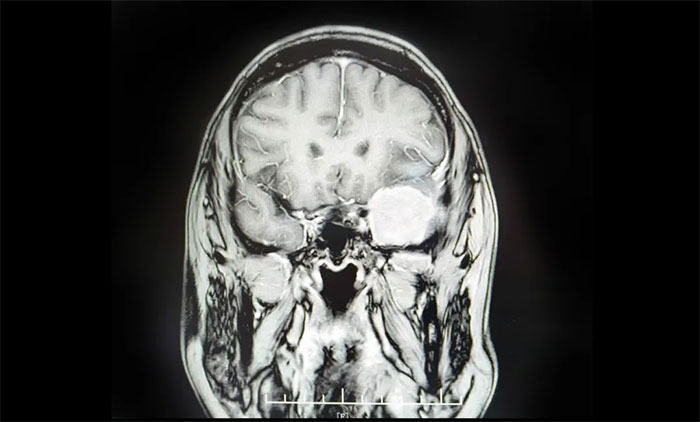

張女士的病例極具警示意義。兩年前體檢發(fā)現“顱內占位”,因擔心手術風險選擇了保守治療。今年6月下旬,她突發(fā)持續(xù)性頭暈,兩周未緩解,預感不妙,遂前往上海藍十字腦科醫(yī)院求診。

檢查證實為左側蝶骨嵴腦膜瘤。該腫瘤位置極其兇險:緊貼左側語言中樞和運動皮層,損傷可能導致失語或癱瘓;與大腦關鍵供血主干——大腦中動脈(MCA)及重要靜脈竇緊密粘連;深埋于蝶骨嵴顱底,手術視野狹窄,難度巨大。

最終,盧云鶴博士團隊迎難而上,成功運用翼點入路手術,順利切除了這枚4.5公分的巨大腫瘤。術后第二天,患者即肢體活動自如,言語清晰流暢,無新增神經功能損傷,目前正在康復中。